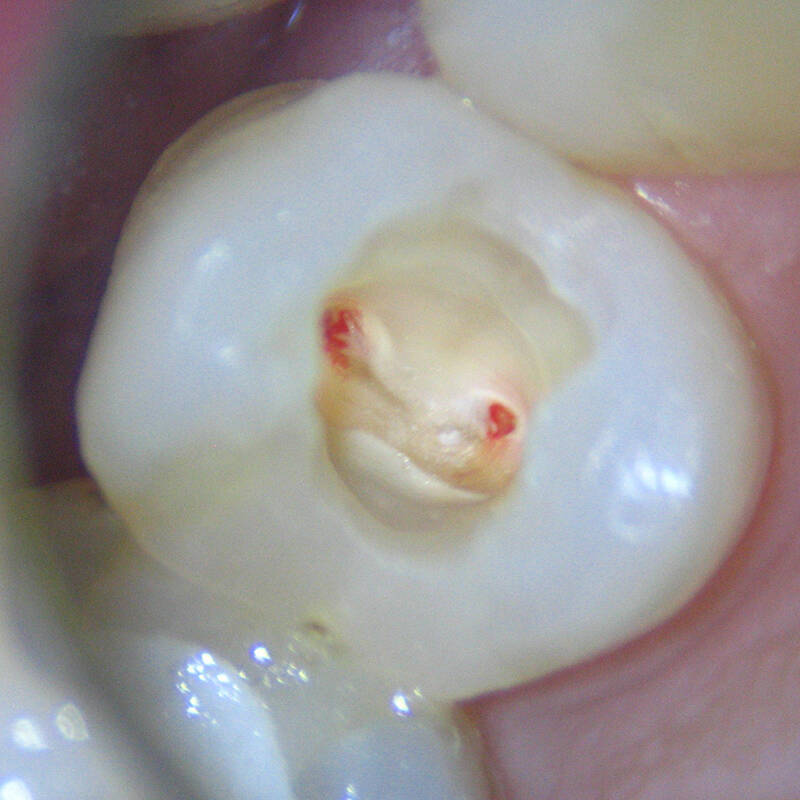

- Diagnóstico: O dentista realiza exames clínicos e de imagem para avaliar a condição do dente e da polpa.

- Remoção da Polpa: Quando o nervo está danificado (inflamado, infectado ou morto), ele é removido do interior do dente.

- Limpeza e Desinfecção: O canal radicular é cuidadosamente limpo e desinfetado para remover qualquer resquício de tecido infectado.